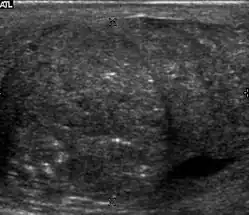

Seminoma is the most common tumor type in cryptorchid testes. The risk of developing a seminoma is increased in patients with cryptorchidism, even after orchiopexy. There is an increased incidence of malignancy developing in the contralateral testis too, hence sonography is sometimes used to screen for an occult tumor in the remaining testis. On US images, seminomas are generally uniformly hypoechoic, larger tumors may be more heterogeneous [Fig. 3]. Seminomas are usually confined by the tunica albuginea and rarely extend to peritesticular structures. Lymphatic spread to retroperitoneal lymph nodes and hematogenous metastases to lung, brain, or both are evident in about 25% of patients at the time of presentation.